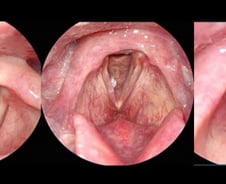

먹고, 말하고, 마시는 공간에 발생하는 암이 두경부암이다. 자칫 장애를 유발하지만 진단, 추적 관찰이 쉬워 일찍만 발견하면 완치할 수 있다. 흡연과 음주, 구내염, 노화, 바이러스 등 두경부암을 일으키는 원인은 다양한데, 최근 발생 빈도가 늘었다. 서울시보라매병원 이비인후과 이비인후과 이도영 교수에게 두경부암은 무엇이고 그 원인과 종류, 치료 방법을 들어본다. ━환자 90% 이상은 술·담배 즐기다 발병━두경부암은 뇌암·안구암을 제외하고 머리·목에 생기는 모든 암을 일컫는다. 두경부 안에 있는 각 조직(혀·코·후두·성대)에 발생하는 암의 빈도가 낮기 때문에 '두경부'라고 통칭한다. 두경부암은 어느 부위에 발생하든 '점막'이라는 똑같은 세포에서 발생하므로 치료 방법, 병기, 수술 방법, 약물, 방사선 치료 등이 공통으로 이뤄진다. 우리나라에서 두경부암은 전체 암 발생 건수의 약 5%에서 매년 진단된다. 두경부암을 각각의 특별한 구강암, 후두암으로 쪼개 보면 훨씬 낮은 비율로 진단되고 있